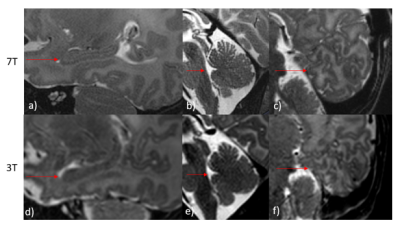

Across the cohort, additional detail of anatomical or pathological features were seen in the 7T scans compared to typical 3T scans. In all 7 participants, image quality of the 7T scans was observed to be equivalent or superior to 3T scans. These included: specific improvements in visualisation of the hippocampus, cerebellum vermis and cortical folding of the occipital lobe, (Figure1). 7T was also able to demonstrate pathologies and offered more information than 3T, such as improved visualization of cystic septi in periventricular leukomalacia (PVL)(Figure2).

Figure 1: 7T (a-c) and 3T (d-f) T2W images of a 40+1 week male newborn infant (a, d) and 41+1 week female newborn infant (b,c,e,f). Note the clearer depiction of the hippocampus in 1a compared to 1d, of the cerebellum vermis in 1b than 1e, and improved overall cortical folding in occipital lobe in 1c than 1f.